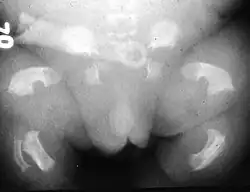

Radiogram of a baby born with thanatophoric dwarfism | |

Infants with this condition have disproportionately short arms and legs with extra folds of skin. Other signs of the disorder include a narrow chest, small ribs, underdeveloped lungs, and an enlarged head with a large forehead and prominent, wide-spaced eyes. Thanatophoric dysplasia is a lethal skeletal dysplasia divided into two subtypes. Type I is characterized by extreme rhizomelia, bowed long bones, narrow thorax, a relatively large head, normal trunk length and absent cloverleaf skull. The spine shows platyspondyly, the cranium has a short base, and, frequently, the foramen magnum is decreased in size. The forehead is prominent, and hypertelorism and a saddle nose may be present. Hands and feet are normal, but fingers are short. Type II is characterized by short, straight long bones and cloverleaf skull.[1] It presents with typical telephone-handle shaped long bones and H-shaped vertebrae.

Infants with type 1 thanatophoric dysplasia also have curved thigh bones, flattened bones of the spine (platyspondyly) and shortened thoracic ribs. Note: Prenatal ultra-sound images of the ribs sometimes appear asymmetrical when in fact they are not. In certain cases, this has caused a misdiagnosis of osteogenesis imperfecta (OI) type II.